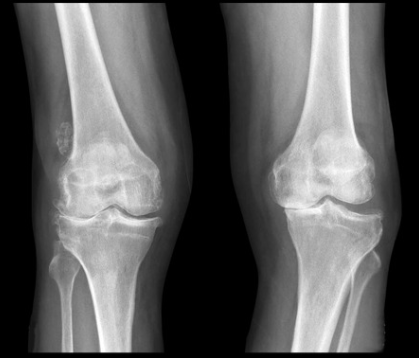

変形性膝関節症の診断

膝の痛みの場所や圧痛の有無、可動域や水が溜まっているかなどをチェックします。またレントゲンで膝の関節の隙間が減っていないか、変形がないかを確認します。

変形性質関節症の治療

まずは炎症を抑えることが重要です。そのためには炎症を抑える薬、湿布、塗り薬、サポーターなどで治療します。またヒアルロン酸の注射を行い、骨同士ぶつかっている膝に潤滑液を注入し、炎症と痛みの軽減を図ります。並行してリハビリをや物理療法を行い、総合的に治療していきます。